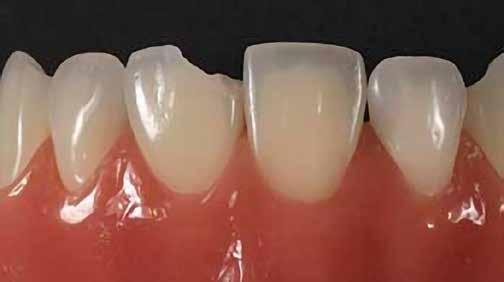

A fogászati kezelések során manapság már nem kizárólag az esztétikai megjelenés helyreállítására törekszünk. Sokszor a kedvezőtlen esztétikai megjelenés hátterében álló okok következményes módon a fogazat funkcionális működését is károsítják, így a kezelések során ezeknek a helyreállításával is foglalkoznunk kell. A különböző funkcionális és esztétikai diszkrepanciák kezelésére számtalan módszer létezik, ám ezen fogászati beavatkozások mindegyikében közös, hogy a kivitelezésük során nagyon szoros együttműködésre van szükség a kezelést végző fogorvos és a munkáját segítő fogtechnikus között. Az alábbi esetbemutatás során egy fiatal hölgypáciens fogazatának héjak alkalmazásával történő esztétikai és funkcionális rehabilitációját szeretnénk ismertetni.

A 19 éves hölgypáciens azzal a kéréssel jelentkezett a rendelőnkbe, hogy szebb fogakat szeretne. Az első konzultáció alkalmával megkérdeztük, hogy mi zavarja leginkább a fogazatának jelenlegi megjelenésében, valamint azt is megbeszéltük vele, hogy milyen végeredmény elérése esetén lenne maradéktalanul elégedett. Ebben az esetben a kezelési célokat az alábbiakban határoztuk meg:

A páciens fogazata esztétikai megjelenésének és funkcionális működésének a lehető legtöbb, saját foganyag megtartása mellett történő helyreállítása (1. és 3. ábra).

A lehető legideálisabb esztétikai végeredmény elérése érdekében néhány esetben a fogak alakjának módosítá -

A kezelés megtervezése során kifejezett jelentősége van annak, hogy jó kommunikáció legyen a páciens, a fogorvos és a fogtechnikus között. A páciens leendő fogazatának természetes megjelenését a kezelésben részt vevő team szakmai felkészültsége, gyakorlati tapasztalata és a kezelés sikerességének irányába történő elkötelezettsége biztosítja. A beavatkozások megkezdése előtt megtörtént a páciens anamnézisének a felvétele, valamint a klinikai kivizsgálását is elvégeztük. Ezt követően lenyomatokat készítettünk a kiindulási állapotról, majd a kiindulási helyzetet extra- és intraorális fotók segítségével is rögzítettük (13. a-c. ábra).

A kezeléstervezés egyik legfontosabb lépése a mock-up elkészítése. A mock-up alapjául szolgáló wax-up-ot (felviaszolás) is ugyanolyan részletességgel kell a fogtechnikusnak elkészíteni, mintha azok már a végleges fogpótlások alapjául szolgáló mintázatok lennének. A mock-upnak nagyon pontosan kell illeszkednie, valamint a tervezett fogpótlás meg-

jelenését is rendkívül élethűen kell reprezentálnia. Ahhoz, hogy a páciens mock-uppal kapcsolatos első benyomásai kedvezőek legyenek, a mock-up színének a páciens „szemfehérjének” színével meg kell egyeznie. A kezelési cél páciens által történő elfogadása és a tervezett eredménnyel kapcsolatos „wow-effektus” kialakulása nagyban függ a páciensben az első megtekintés során kialakult első benyomásoktól.

Az eddigi tapasztalataink szerint a páciensek jelentős többsége egyértelműen kifejezi az elégedettségét, ha a mock-up megfelel az eredeti elképzeléseiknek. A bemutatásra kerülő esetben is ez történt. A tervezett végeredmény megtekintését követően a páciens azonnal kérte az általunk javasolt kezelési tervben ismertetett beavatkozások elvégzését. A héjak alapanyagául az Ivoclar Vivadent által gyártott A1-es színű Telio CS kerámiát javasoltuk. Az anyagválasztás hátterében az állt, hogy ez az anyag nagy keménységgel rendelkezik, valamint az, hogy a felszínét nagy simaságúra lehet polírozni. A páciens rendkívül fiatal életkora is azt a terápiás koncepciót erősítette, hogy a kezelés során lehetőség szerint kizárólag non-invazív beavatkozásokat alkalmazzunk.

A páciens már kezdetben is rendkívüli érdeklődést mutatott a preparálást nem igénylő (non-prep), héjakkal történő ellátással kapcsolatban. Ennek a terápiás modalitásnak az előnyei közé tartozik, hogy a fogakat egyáltalán nem, vagy csak minimál invazív módon kell preparálni, nincs szükség ideiglenes héjak készítésére, a héjak alapanyagául szolgáló kerámia nem hajlamos az elszíneződésre, nem jellemző a beavatkozások elvégzését követően jelentkező posztoperatív szenzitivitás, valamint hogy ezzel a módszerrel rendkívül kedvező esztétikai végeredményt lehet elérni. A fenti előnyök rendkívül meggyőzően hatottak a páciensre. A döntése során azt is figyelembe vette, hogy amennyiben ezeket a viszonylag költséges restaurátumokat választja, akkor ez a kezelés végösszegét is jelentős mértékben befolyásolja.

A kezelés során az jelentette a legnagyobb kihívást, hogy a héjakkal ellátott fogak élethűen utánozzák a természetes fogazat megjelenését. A fogpótlás színének, valamint a restaurátumok felszíni textúrájának és alakjának harmonikusan kell a páciens arcesztétikájához és karakteréhez illeszkednie.

A tényleges protetikai ellátás megkezdése előtt a páciens mosolygás közben látható fogait otthoni fogfehérítés keretei között a kérésének megfelelő A1-es fogszín eléréséig fehérítettük. A fehérítés során a későbbiekben héjakkal ellátásra kerülő fogak színén nem változtattunk. A fogak előkészítése részeként csupán a két felső nagymetsző (1.1,2.1) incizális élét kellett kismértékben redukálni. A többi felső front fog (1.3,1.2,2.2,2.3) nem került preparálásra.

A platinafólia technikát 1896 óta alkalmazzák. Napjainkra az eredeti eljárás már kismértékben módosításra került, de lényegében ugyanazzal a módszerrel történik a platinafóliára készülő koronák és héjak elkészítése. A minimál invazív fogászat egyre szélesebb körben történő elterjedésének köszönhetően ez az eljárás a reneszánszát éli. A pácienseink egyre gyakrabban szeretnék a fogaik alaki, színi vagy helyzeti rendellenességeit a lehető legkisebb saját foganyagveszteség árán korrigáltatni. Az eljárás során 0,025 mm vastag 99,9%-os tisztaságú platinafólia kerül alkalmazásra. Amennyiben a megfelelő technikai háttér és a beavatkozások elvégzéséhez szükséges elméleti és gyakorlati szaktudás is rendelkezésünkre áll, akkor semmi sem állhat az utunkba a pácienseink új mosolyának kialakítása során.

A módszer első lépéseként a gipszből kiöntött csonkokat platinafóliával borítjuk (5. ábra). Az adaptálását követően a felhelyezett fóliát óvatosan eltávolítjuk, felhevítjük, majd ismét visszahelyezzük a csonkokra. Ezt követően történik meg az első kerámiaréteg felvitele (Waschbrand). Az első égetés során csupán egy nagyon vékony réteg kerámia kerül a fólia felszínére (6. ábra). Amikor az égetést követően ezt

a kezdetleges kerámiavázat visszahelyezzük a csonkokra, a kerámia anyagában vékony repedések alakulnak ki. A végleges restaurátum elkészítéséhez szükséges kerámia „köpeny” ekkor áll készen a további kerámiarétegek felvitelére és kiégetésére (opaker réteg, dentin- és zománcmassza felvitele) (7-10. ábra). A készülő fogpótlás végső formai megjelenése rétegenként kerül kialakításra.

A második égetés során szintén csupán egy nagyon vékony réteg transzlucens opalmassza kerül felhelyezésre. A restaurátum formai megjelenésének és a felszíni textúrák kialakítására csak ezt követően kerül sor. A fényégetés során nem alkalmazunk glazúrmasszát. A készre vitel során elérni kívánt, magas fényű polírt kézi eszközök alkalmazásával alakítjuk ki. A restaurátumok végső kidolgozását követően a platinafóliát egy csipesz segítségével óvatosan eltávolítjuk, majd a kifejezetten vékony héjakat a kontroll mintára helyezzük. Ezt követően a pótlások megfelelő illeszkedésén kívül a funkcionális elmozdulások közben kialakuló érintkezéseket és a kontaktpontokat is ellenőrizzük. Az ilyenkor esetlegesen szükségessé váló korrekciók elvégzésére a Ducera® LFC (Dentsply Sirona) kerámiaanyagot használjuk. A kész munka fogorvosi rendelőbe való szállítása előtt kifejezett jelentőséggel bír az elkészült restaurátumok gondos becsomagolása. Az átadni kívánt fogpótlások sérülésmentes szállíthatóságának biztosítása elengedhetetlen az eddigi munkánk védelme szempontjából.

A héjak átadását követően kialakuló állapot valósághű módon történő bemutatása érdekében próbapasztát alkalmaztunk (Try-In-Paste; Variolink® Esthetik Try-In-Paste, Ivoclar Vivadent) (11. ábra). A próba során ellenőrizzük a héjak színét, formáját és transzparenciáját. A próbapaszta alkalmazásának egyik lényeges pontja, hogy a paszta színe egyezzen meg a végleges beragasztás során alkalmazni kíván ragasztóanyag színével. A héjak végleges rögzítése során mindig adhezív rendszereket használunk.

A preparálást nem igénylő héjak általában nagyon vékonyak, és sajnálatos módon ebből adódóan a végleges átadásuk előtt történő előkészítés során könnyen eltörhetnek. Csupán a páciensek saját fogain történő végleges rögzítés révén kapják meg azt az alátámasztottságot, amely a végleges töréssel szembeni ellenálló képességüket biztosítja. A fogpróba során a héjakat egyesével a fogakra helyezzük, és ellenőrizzük a pontos illeszkedésüket, valamint az approximális kontaktpontok megfelelőségét. Amenynyiben mindent rendben találtunk, úgy hozzákezdhetünk a héjak adhezív módszerrel történő rögzítéséhez szükséges előkészületek elvégzéséhez. Első lépésként a héjak elhorgonyzásul szolgáló fogak abszolút izolálását követően, meggyőződünk a ragasztási felület leszáríthatóságáról. Ezt követően az adhezív rögzítés során felhasznált fogfelszínt – az alkalmazni kívánt adhezív rendszer

nak megfelelően – előkészítjük (orthofoszforsavval történő savazás, lemosás, szárítás és bond réteggel történő fedés). Ezzel egyidejűleg a ragasztásra kerülő héjak is előkészítésre kerülnek (hidrofolysavval történő savazás, lemosás, szárítás, szilanizálás, bond réteggel történő fedés, és végül az alkalmazni kívánt ragasztóanyag felvitele). Ezután a héjakat a fogak felszínén egyesével pozicionáljuk, majd néhány másodpercen keresztül polimerizációs lámpa segítségével megvilágítjuk. Ezt követően a kifolyó ragasztófelesleget eltávolítjuk, majd elvégezzük a restaurátumok végső polimerizálását. A héjak végleges rögzítését követően az esetlegesen visszamaradt ragasztómaradványok eltávolításra kerülnek, valamint ellenőrizzük az okklúzió és artikuláció közben létrejövő fogérintkezéseket. Az optimális esztétikai eredmény biztosítása érdekében kiemelt jelentősége van a papillák helyreállításának (rózsaszín esztétika). A modern fogorvoslás egyik kiemelt célja a fehér- és rózsaszín esztétika közti harmonikus egyensúly megteremtése. A papillák színe, nagysága és szimmetrikus megjelenése meghatározó szerepet tölt be a rózsaszín esztétika kialakításában. Az íny lefutása ugyancsak rendkívül jelentős mértékben befolyásolja a páciens fogazatának esztétikus megjelenését.

A cikkünkben bemutatásra kerülő eset ellátása során preparációt nem igénylő héjak készítése mellett döntöttünk. A héjak készre vitele során a platinafólia technikát alkalmaztuk. Annak ellenére, hogy az elkészítésre kerülő héjak rendkívül vékonyak, és ezáltal a végleges rögzítésük előtt jelentős törésveszéllyel állunk szemben, összességében mégis olyan minimál invazív kezelési eljárásnak számítanak, amely segítségével kifogástalan esztétikai eredményeket lehet elérni. A fent leírtak alapján bátran javasoljuk e módszer alkalmazását.